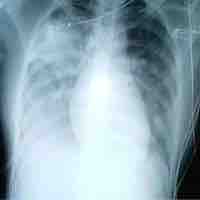

Medical Importance of Viruses

Viruses are obligate intracellular parasites that hijack a host cell's machinery to replicate, thereby causing disease.